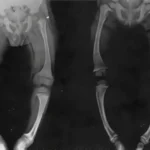

Las fracturas relacionadas con la osteoporosis suelen ser el primer signo clínico de la enfermedad, y pueden manifestarse de diferentes maneras, dependiendo de la localización y la gravedad de la fractura. Una de las formas más comunes en que la osteoporosis se hace evidente es a través de fracturas vertebrales. Estas fracturas ocurren cuando una o más vértebras de la columna vertebral se comprimen o colapsan debido a la fragilidad del hueso, lo que puede desencadenar dolor en la espalda de intensidad variable. El dolor de espalda puede ir desde una molestia leve hasta un dolor severo y debilitante, que puede afectar significativamente la capacidad del individuo para realizar actividades cotidianas.

Las fracturas vertebrales y de cadera son las más prevalentes en los individuos con osteoporosis, y ambas tienen un impacto significativo en la salud y la calidad de vida. Las fracturas vertebrales no solo causan dolor físico, sino que también pueden afectar la función pulmonar y aumentar el riesgo de otras complicaciones. Además, las fracturas de cadera son especialmente preocupantes debido a su alta tasa de mortalidad asociada, particularmente en personas mayores. Estas fracturas suelen requerir intervención quirúrgica, y la recuperación puede ser prolongada, con un riesgo elevado de complicaciones, como infecciones, trombosis venosa profunda y problemas relacionados con la movilidad.

Es necesario considerar además la realización de pruebas complementarias, como radiografías, tomografías computarizadas o resonancias magnéticas, para confirmar el diagnóstico de fracturas y evaluar el grado de pérdida ósea. Además, la densitometría ósea es una herramienta diagnóstica clave que permite medir la densidad mineral ósea y valorar el riesgo de futuras fracturas. A través de estas pruebas, los médicos pueden clasificar la severidad de la osteoporosis y decidir el tratamiento más adecuado.